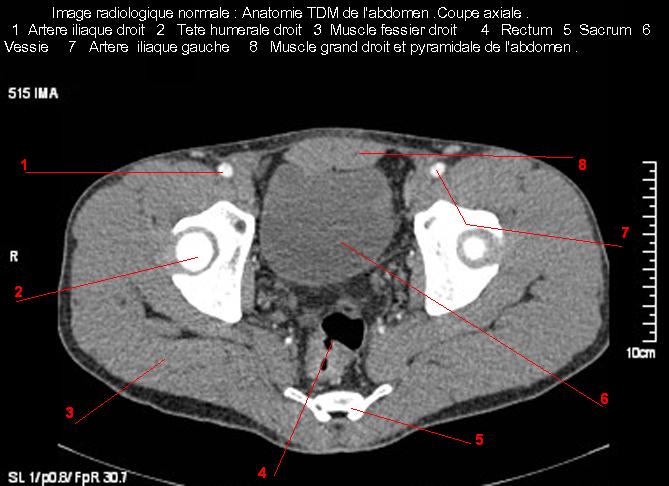

Images radiologique normale de l'abdomen et tube digestif en coupe axiale ( CT scanner )  :

Coupe axiale     Coupe frontale      Coupe  sagitale